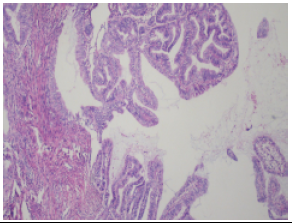

(子宫内膜)子宫内膜复杂性增生,伴不典型增生,局灶癌变。

(全子宫+双附件,双侧盆腔淋巴结,腹主动脉旁淋巴结,腹水)中高分化子宫内膜样腺癌,浸润深度<1/2肌壁,大小5.2cm*4.5cm*1.6cm;癌累及子宫峡部粘膜;未见脉管及神经侵犯;左右宫旁及阴道断端阴性;慢性宫颈炎;双侧输卵管黏膜慢性炎;双侧卵巢未见著变;淋巴结未见癌转移(左盆腔0-6,右盆腔0-10,腹主动脉旁0-2);腹腔冲洗液刷片未见瘤细胞。

免疫组化:

ER(强阳,60%),Ki67(+10%),P53(野生型),PR(中阳,8%),PD-L1(CPS<;1,E1L3),P16(+),Vimentin(+),Pax-8(灶+),MLH1(+),MSH2(+),MSH6(+),PMS2(+),WT-1(-)。